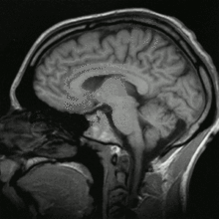

• Imagen por Resonancia Magnética (IRM)

Imagen por Resonancia Magnética (IRM)

Una imagen por resonancia magnética (IRM), es una técnica no invasiva para obtener información sobre la estructura y composición del cuerpo a analizar.